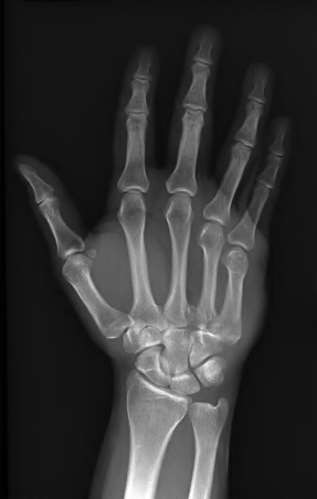

A 20-year-old park ranger trips and falls onto his right wrist with the wrist in extension and pronation. The local urgent care orders both radiographs and a CT, which you review and determine to be normal. The patient complains of ulnar-sided wrist pain. On exam, his tenderness is localized to the fovea. Ulnar deviation also causes him pain. There is no snapping sensation with wrist supination, flexion, and ulnar deviation. He otherwise has 5/5 strength to his first dorsal interosseous muscle with 4mm static two-point discrimination on the ulnar side of the 4th digit. Which of the following injuries is most likely responsible for his symptoms and exam?

volar tenderness along the flexor sheath